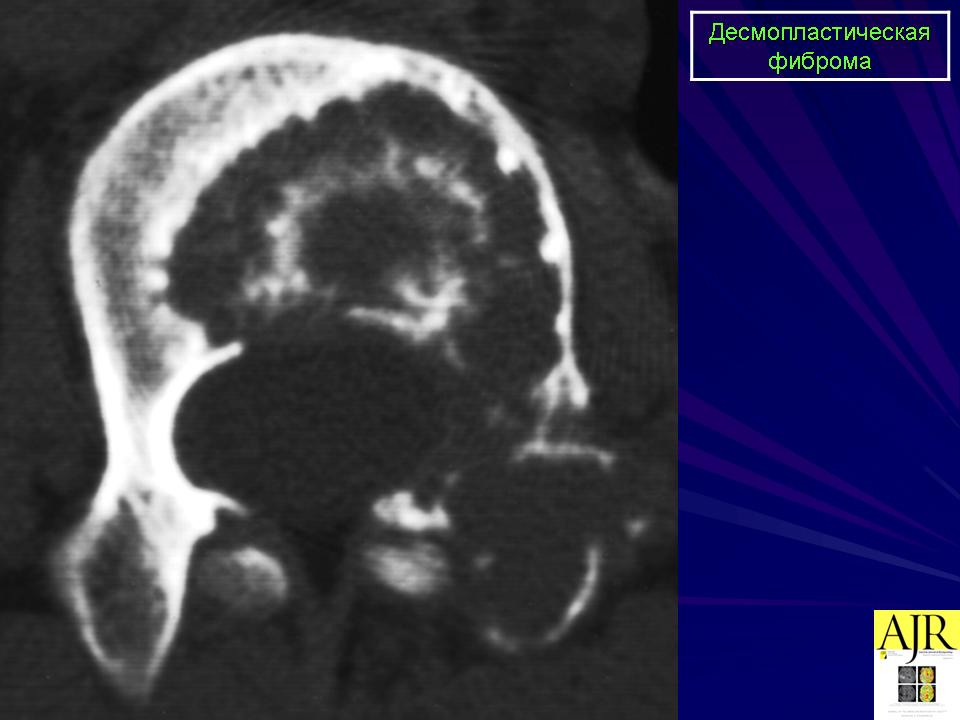

Десмопластическая фиброма редкая локально агрессивная внутрикостная опухоль, характеризующаяся продукцией опухолевыми клетками пучков коллагеновых волокон. Встречается в любом возрасте (чаще у лиц моложе 30 лет), с равной частотой у мужчин и женщин. Локализуется в основном в эпифизах и метафизах длинных костей (бедренная, плечевая, большеберцовые кости), плоских костях (кости таза, лопатка), нижней и верхней челюстях.

Рентгенологически остеолитический очаг, вызывающий вздутие истончённой кортикальной пластинки.

Десмопластическая фиброма